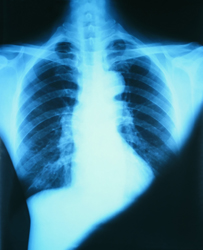

Skeletal dysplasia is a generic term for a range of over 200 conditions that involve the development of bony tissue. The phenotypes range from very mild symptoms to severe and lethal types and include the conditions achondroplasia and neurofibromatosis. The challenge for the European Skeletal Dysplasia Network (ESDN) was to devise a system whereby medical professionals could pool data from research and details of patients' cases. An online consultation and feedback forum could then be created with the overall aim of case characterisation, diagnosis and relevant treatment, if appropriate. The system was developed by Certus Technologies Associates Ltd. Features include secure on-line case detail entry and a discussion system that allows groups of experts to contribute to the review of a case. An important implication is that all European citizens would have equal access to diagnosis and treatment regardless of their geographical status. Moreover, input of data on such a wide scale with feedback means that there could be external quality assessment of laboratory test procedures. Given the range of occurrence of these disorders, a pan-European approach would enable the results of multi-disciplinary research to be translated into improved refined clinical practice. The system can be accessed at http://www.ESDN.org(opens in new window) where comprehensive details of centres and their specialities in terms of diseases and genes screened are given. Practical issues such as submission of radiographs and procedure for referral of a case are detailed. There is also a page for newsletters and the status quo on latest research. Although this particular project dealt with aspects of skeletal dysplasia only, the system may be applied to any group of disorders that warrant online medical analysis. Elements of the system have been incorporated by the Directorate General for Health and Consumer Affairs in several other EU projects.